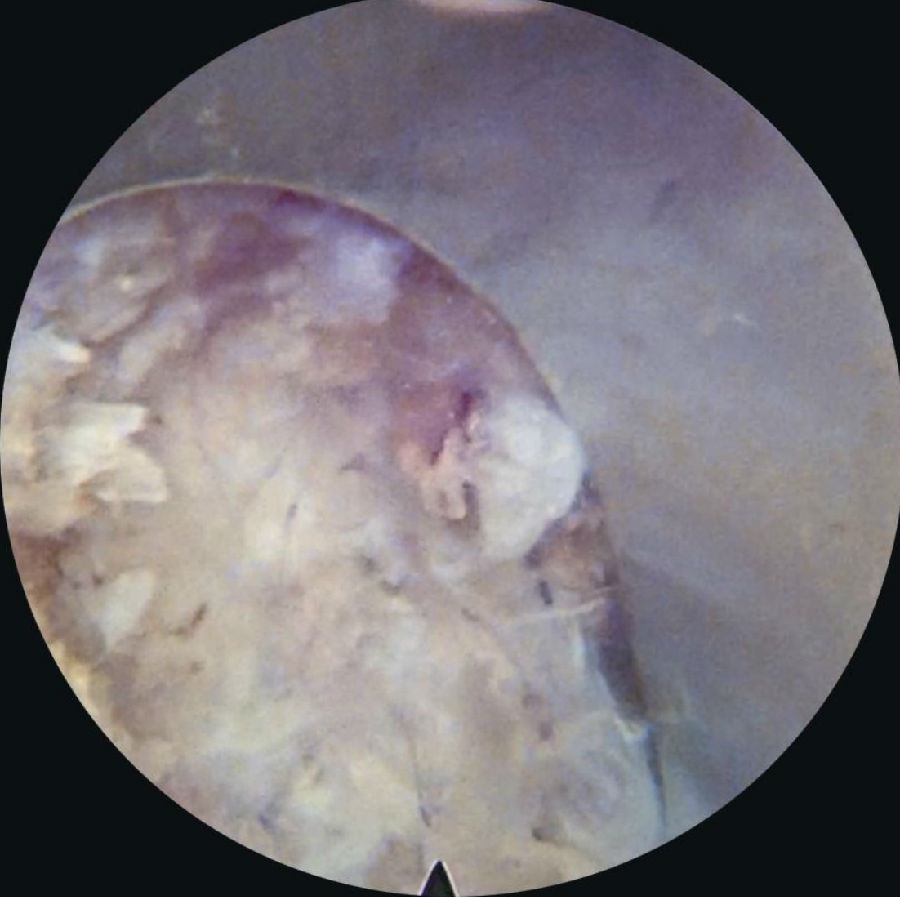

5. 黄韧带扩孔,直视镜下沿黄韧带裂隙将锥形工作套管轻柔地旋转入椎管,可见破碎的髓核组织及纤维环组织。(图30~图35)

6. 确定髓核组织后,用镜下髓核钳将突出髓核组织切除(图36~图40),直至清晰地看到后纵韧带和神经根周围脂肪组织。

7. 双极射频刀头电极在直视下行残存髓核组织消融止血,纤维环破口皱缩成形。(图41)

8. 减压充分的标志是可在镜下看到神经根及硬膜囊随呼吸波动(图42),仔细探查无脱出髓核残留后,退出内镜系统,伤口缝合

图31-图34 篮钳咬除硬膜表面黄韧带;篮钳咬除黄韧带并注意隆起的硬膜囊;

剥离子插入突出髓核并开始旋转工作套管;

继续旋转工作套管,借助套管头端将神经从髓核表面移开

图35-图38 下行根和硬膜囊已经从髓核表面移开;髓核摘除,白色为突出髓核;

髓核摘除过程中;髓核被拖出过程中

图39-图40 大块髓核被拖出;大块髓核被清除过程中

图41-图42 双极射频止血,纤维环成形;髓核摘除后硬膜囊和下行根减压松解